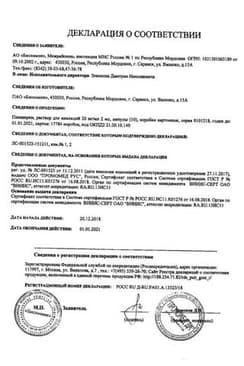

Сертификаты